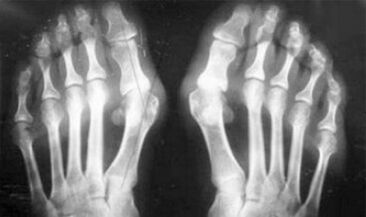

The difference between arthritis and arthrosis of the fingers and hands of the hands is that the first disease is treated and the second is not.With arthritis, the synovial shell and the joint capsule are touched.

The defeat of cartilage and bone tissue occurs only in the late phases in a neglected state.With arthrosis, the cartilage tissue is first hit, and therefore the bone, the inflammation of the synovial membrane is of secondary origin, that is, it develops compared to their background.